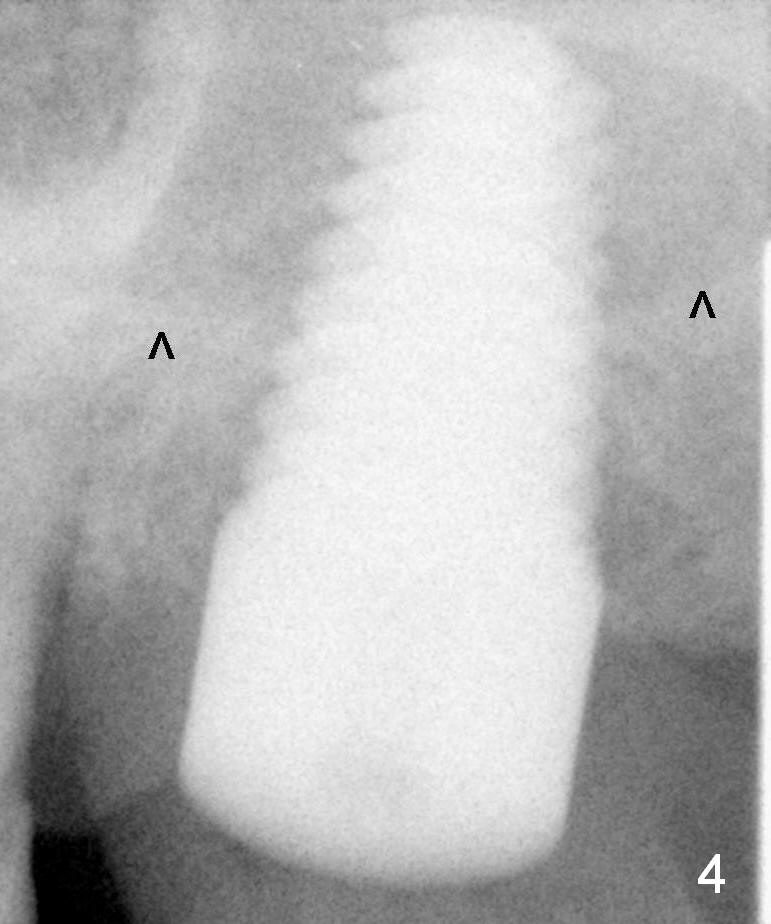

Allograft is pushed into the sinus before placement of a 8x17 mm implant. The insertion torque is between 15 and 20 Ncm (Fig.4). Black arrowheads: sinus floor.